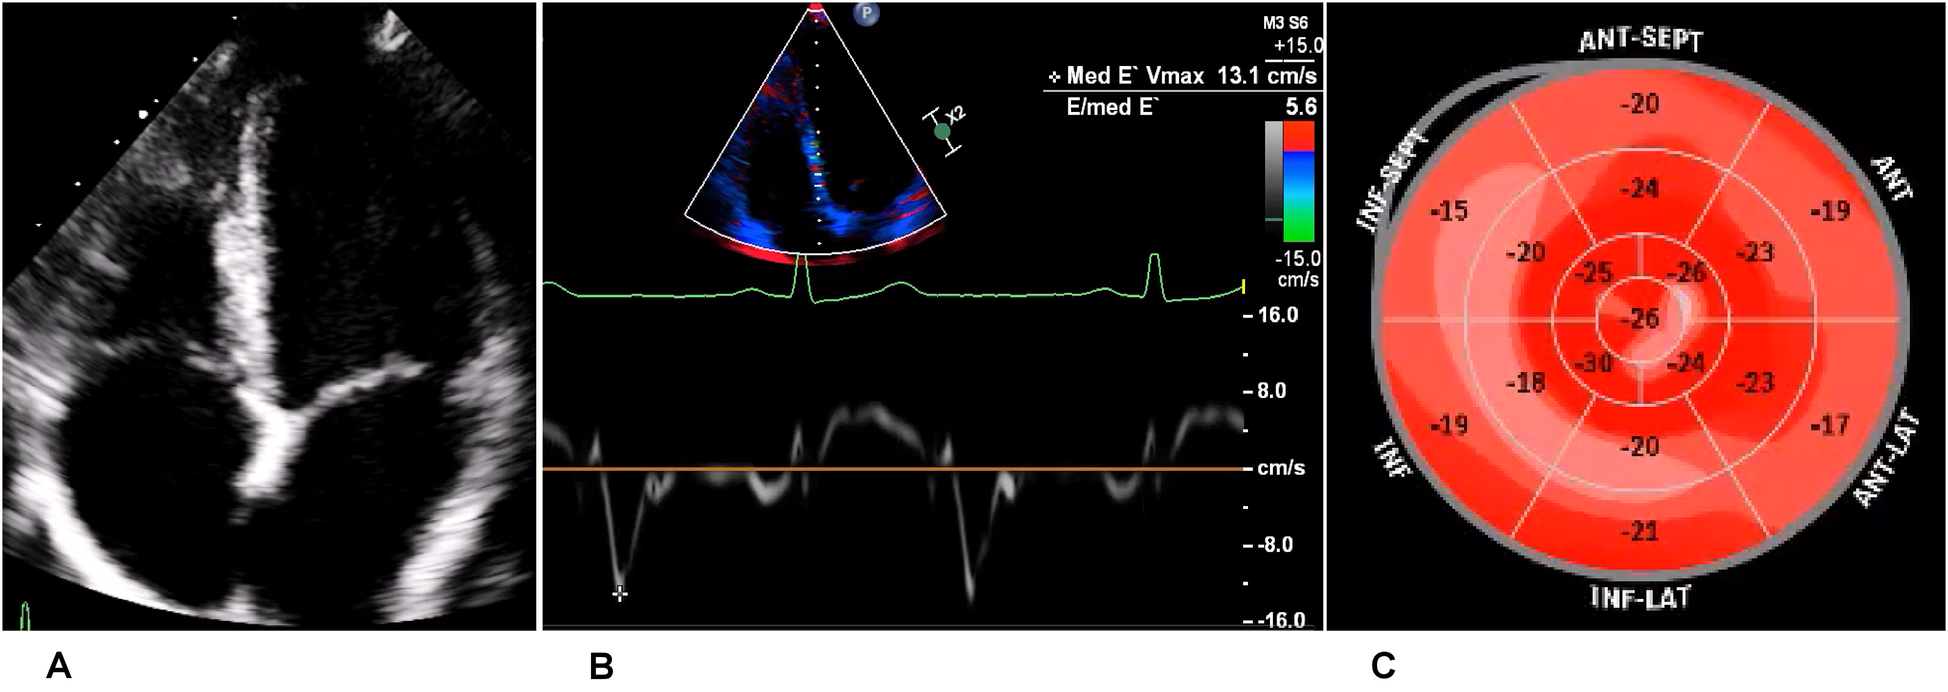

The athlete was lost to follow-up for 1 year (between 19 and 20 years of age), but another echocardiogram, performed at the age of 20 years, showed a slight decline of biplanar LVEF to 58%. However, the athlete had normal diastolic function and no signs of structural heart disease (Figures 5A,B). Strain analysis showed that the athlete’s global longitudinal strain was within the normal range (−22.3%), with reduced values in the inferolateral, inferior, and inferoseptal areas (Figure 5C). Cardiac biomarkers (troponin and NTproBNP) were within the normal range. CMR imaging was performed again and showed reproducible, consistent LGE of the inferolateral wall without edema (Figure 6). However, LVEF had declined from 69% to 53% within 1 year (from age 19 to 20 years). The athlete had, of her own accord, resumed recreational sport activity between 19 and 20 years of age.

Figure 5. Echocardiography of the recreational athlete (ice skating). (A) Four-chamber view on transthoracic echocardiography showing no signs of structural heart disease. (B) Medial tissue Doppler imaging demonstrating velocity within the normal range. (C) Bullseye display of the distribution of longitudinal strain, with more positive values depicting worse strain. This was demonstrated in the inferior, inferolateral, and inferoseptal regions, corresponding to the LGE on magnetic resonance imaging.